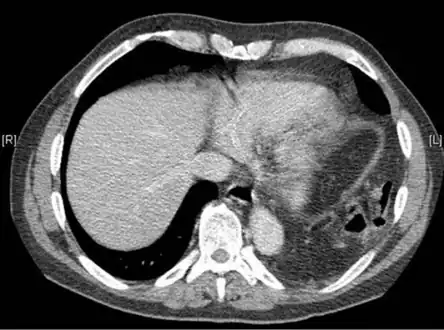

- Bilateral blunt diaphragmatic rupture a) confirmation of intrathoracic herniation indicates left hemidiaphragmatic rupture b) post operative image shows elevation of right hemidiaphragm adding suspicion of right diaphragmatic rupture

- Axial lower chest CT scan showing bowel herniation due to left diaphragmatic rupture